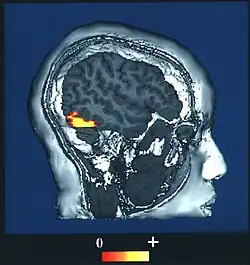

MRI rejestruje jedynie statyczny obraz struktury mózgu. Założeniem fMRI było rozszerzenie działania MRI o rejestrację zmian funkcjonalnych spowodowanych przez aktywność neuronalną. Wraz ze wzrostem tej aktywności w danym rejonie mózgu, rośnie także zużycie we krwi energii i tlenu, który przenoszony jest w cząsteczkach hemoglobiny. W momencie dotarcia do miejsca przeznaczenia, tlen zostaje uwolniony i dociera do mitochondriów, gdzie użyty jest do produkcji ATP. Cząsteczka hemoglobiny związana z tlenem, czyli oksyhemoglobina, ma własności diamagnetyczne i nie wpływa na czas relaksacji atomów wodoru. Po odłączeniu tlenu cząsteczka oksyhemoglobiny przekształca się w cząsteczkę niezwiązaną z tlenem, czyli deoksyhemoglobinę i nabiera właściwości magnetycznych, co powoduje skracanie czasów relaksacji atomów wodoru oraz lokalną zmianę jasności w obrazie MRI[4]. Aby wyrównać braki spowodowane pobraniem tlenu przez neurony, krew natlenowana dociera do aktywowanych miejsc, gdzie zastępuje krew nieutlenowaną. Oksyhemoglobina może dotrzeć do aktywowanego obszaru w czasie 3-5 sekund, a jej ilość przewyższa tę zużytą przez neurony. Powrót do pierwotnego stężenia deoksy- i oksyhemoglobiny zajmuje 10-20 sekund[5].

Ostatecznego powiązania aktywności neuronalnej z metabolizmem hemoglobiny i ideą rozszerzenia techniki MRI z tymi właściwościami dokonał w 1990 roku fizyk Seiji Ogawa, który w czasie badań na mózgach szczurów zauważył różne zachowanie oksy- i deoksyhemoglobiny. W przeprowadzanych przez niego eksperymentach manipulował stężeniem nieutlenowanej hemoglobiny w mózgach badanych gryzoni przez zmianę stężenia tlenu we wdychanym przez zwierzęta powietrzu. W powietrzu o 100-% stężeniu tlenu szczegółowa anatomia żył była widoczna na zdjęciach jako ciemne obszary, z kolei w powietrzu o 90-% zawartości tlenu i 10-% zawartości dwutlenku węgla, żyłkowe struktury były mniej widoczne. Intensywność obrazu zmieniającą się zależnie od poziomu deoksyhemoglobiny nazwano Blood Oxygenation Level Dependent (BOLD). Ogawa postanowił wykorzystać to zjawisko w celu stworzenia MRI rozszerzonego o BOLD traktowanego jako naturalny kontrast. Kilka lat później metodę tę wykorzystano do zbudowania skanera do zastosowań szpitalnych[9].